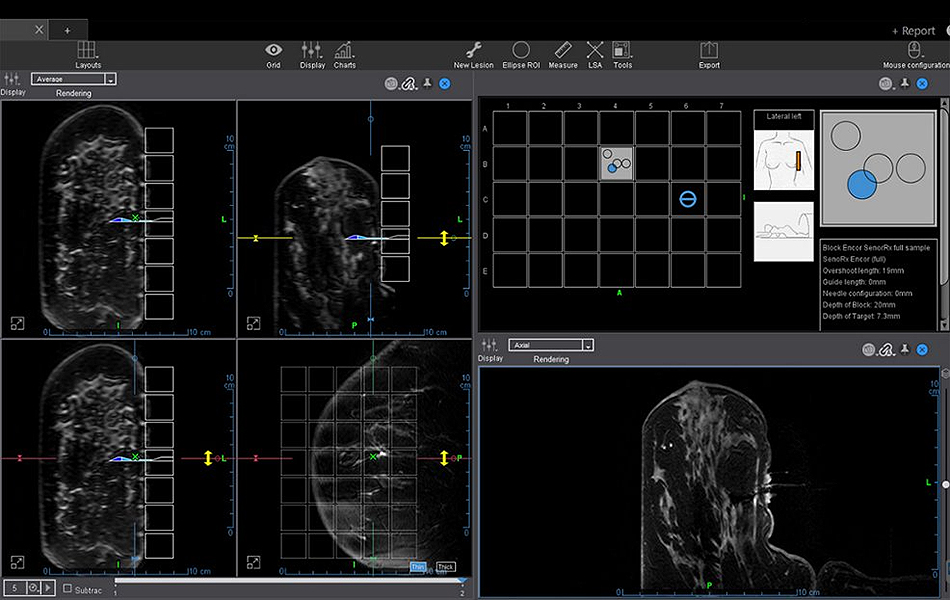

Olea Sphere® – MR Breast Biopsy (BreastLoc)

MR Breast Biopsy (BreastLoc) under MRI provides assistance for the planning of breast biopsies, integration of multi-vendor blocks and grid models, automatic localization (coordinates) of the targeted lesion, and exportable report of the biopsy plan.